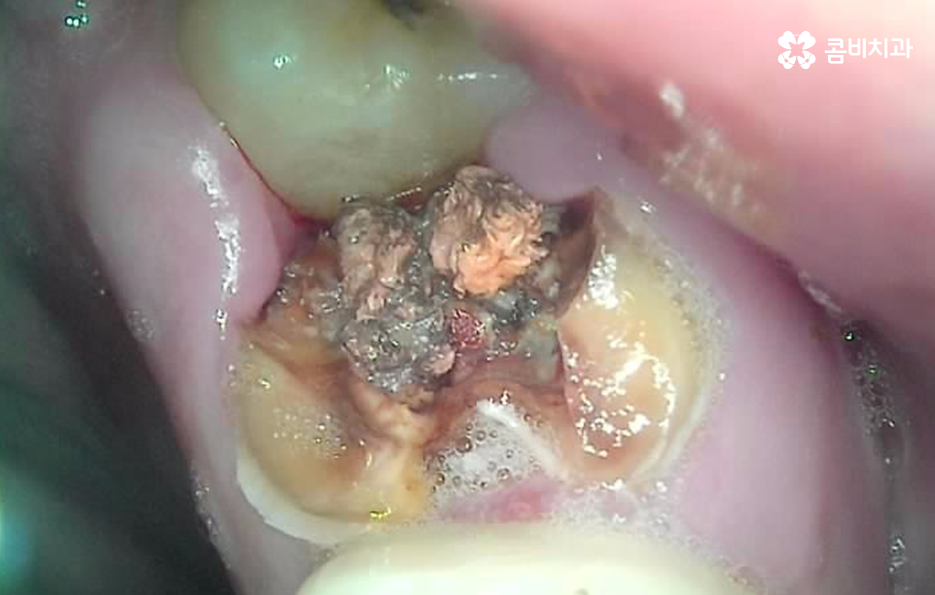

오늘은 자연치아를 결국 잃게 되면 대표적인 사례 중에서 오래된 보철물 혹은 보철물 관리가 잘 안되어 결국 발치로 이어지는 사례에 대해서 알아볼 거예요. 오래된 보철물 속에서 진행되는 2차 충치는 알아차리기도 쉽지 않고 이미 깊어지면 치아 뿌리 쪽으로 충치가 진행되어 발치로 이어지는 경우가 많다는 점에서 보철물 관리의 중요성에 대해서 재인식하는 포스팅이 되길 바라고 있어요

보통 어금니 크라운을 씌운 경우에는 신경치료를 한 후에 크라운을 씌운 경우가 많기 때문에 이미 크라운 속에 충치가 심하게 진행되어도 통증과 같은 증상으로 문제를 잘 못느끼는 경우가 많이 있는데요

치아 문제에 대해서 안아프면 별 문제 없겠지 하고 잘 지내고 있다가 예전에 씌워서 기억도 잘 안나는 크라운이 흔들리거나 냄새, 잇몸 염증 등이 발생하여 치과를 찾게 되었는데 이미 심각한 수준으로 치아 내부에 충치가 진행되어 결국 발치에 이르게 되는 경우가 많이 있어요

크라운 혹은 오래된 보철물 내부에 2차 충치가 발생된 경우에 자연치아를 보존할 수 있는지에 대한 판단은 엑스레이 만으로 진단할 수 있는 문제는 아니며 치아 내부에 충치가 어느정도나 진행되었고 잔존하는 치아의 양이 어느정도나 되는지에 따라서 발치 혹은 치아 보존 치료에 대한 판단을 할 수 있어요

이미 신경치료를 했던 치아라고 해도 보철물 제거 후에 충치를 잘 치료하고 재신경치료를 통해서 치아를 보존할 수 있는 경우가 있고 발치 후 임플란트를 해야하는 경우도 있는데요

이러한 판단 기준은 치아 내부에서 충치가 발생되었을 때 충치가 얼마나 치아 뿌리 쪽으로 깊어졌는지 혹은 살릴 수 있는 치아가 얼마나 잔존하는지에 따라서 다르며 치과의사 역시도 치아 속을 확인해보고 충치를 제거해봐야 알기 때문에 치과의사의 숙련도, 경험도 중요하겠지만 치과의 내원 시점이 무척이나 중요하기 때문에 보철물이 오래된 경우에는 꼭 주기적으로 치과 검진을 하시고 의사의 소견 하에 크라운의 교체가 필요하다면 문제가 커지기 전에 재치료를 적절히 받는 것이 자연치아 보존에 중요할 거예요